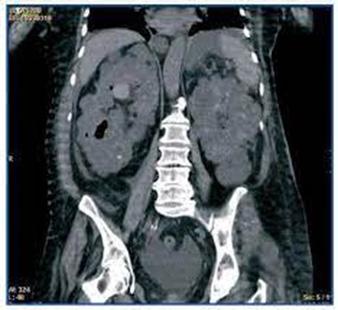

♦ Microangiopatía trombótica

♦ Estenosis de la arteria renal

♦ Nefritis tubulointersticial crónica

♦ Infecciones del tracto urinario / pielonefritis